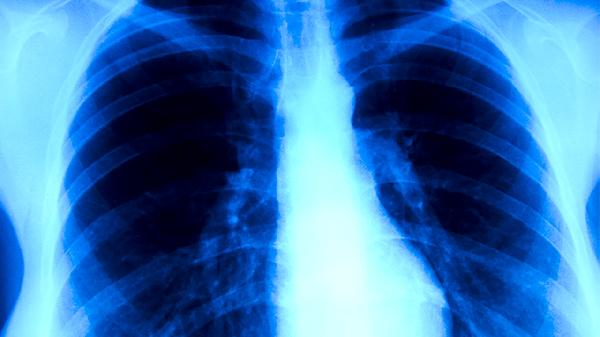

体检CT一般可以查出肺结核。肺结核是由结核分枝杆菌感染引起的慢性传染病,CT检查能清晰显示肺部病变特征,对肺结核的筛查和诊断有重要价值。

CT检查通过高分辨率成像可发现肺结核的典型表现,如肺上叶尖后段或下叶背段的斑片状、结节状阴影,部分伴有空洞形成或钙化灶。活动性肺结核常表现为边缘模糊的渗出性病灶,陈旧性肺结核则多见纤维条索影或硬结钙化。对于痰涂片阴性的患者,CT还能发现支气管播散病灶或纵隔淋巴结肿大等间接征象。

少数情况下,早期肺结核或免疫力低下患者的粟粒型肺结核可能在CT上表现不典型,需结合结核菌素试验、γ-干扰素释放试验等实验室检查综合判断。艾滋病合并肺结核患者可能出现中下肺野的弥漫性病变,与普通肺结核影像特征差异较大。

建议有结核病接触史或出现咳嗽、低热、盗汗等症状者及时进行CT检查,同时配合痰涂片、痰培养等检测。日常生活中应注意保持室内通风,避免与结核病患者密切接触,加强营养摄入提高免疫力。确诊肺结核后需严格遵医嘱完成6-9个月的规范抗结核治疗,定期复查CT评估疗效。